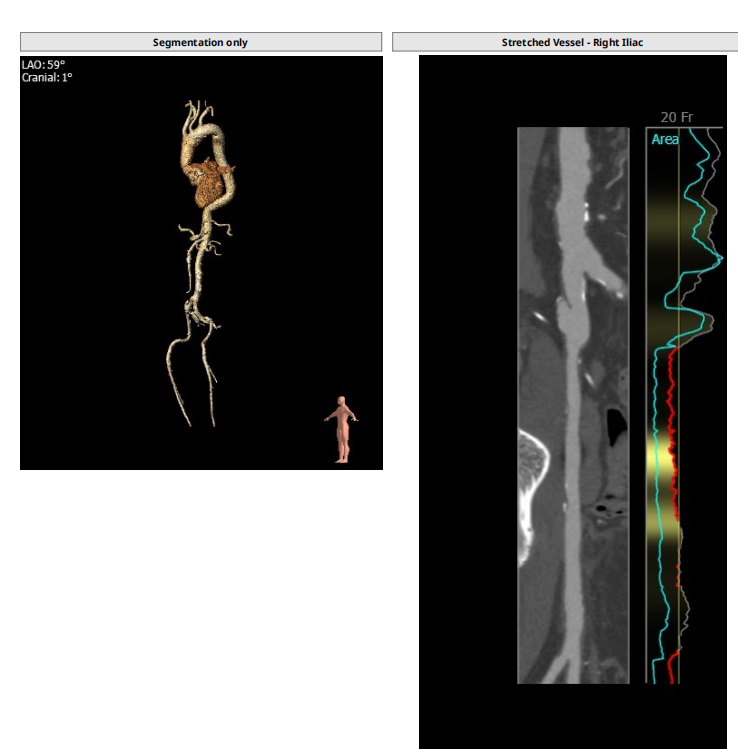

解剖上,这个患者虽然是右无融合的二叶瓣,但是右窦发育较小,形态上接近0型二叶瓣,瓣上钙化中,且集中在左窦,接近左右瓣叶联合部。瓣环及流出道平面较大,而瓣上结构较小,瓣叶联合部距离只有26,这种情况下只能考虑根据瓣上结构进行选择瓣膜。目标瓣膜为26号,为了避免破坏瓣上结构,我们选择26瓣膜的下限20号瓣膜进行与扩张。因为主动脉弓和升主动脉角度问题,没有选择plus。20球囊扩张可以看到左窦钙化很硬,右无联合可以推开,没有反流,故选择26号瓣膜,高位释放。释放后瓣膜下滑到标准位,有明显的腰,故用20球囊进行后扩展。最后造影虽然有中度瓣周漏,但是考虑患者狭窄解除,且升主动脉人工血管限制了瓣膜的流出端,未再行瓣中瓣。术中撤除ECMO,辅助循环约1小时。

现病史:6月前患者无明显诱因出现胸闷气促,伴双下肢水肿,不伴胸痛,不伴头晕头痛,不伴恶心呕吐,不伴咳嗽咳痰,遂于2021—5—13就诊于外院,心脏超声示:主动脉瓣重度狭窄伴轻度关闭不全,二尖瓣、三尖瓣重度反流,全心增大,中度肺高压,CTA 示:1主动脉瓣钙化伴主动脉瓣口狭窄;2.升主动脉置换术后:3.主动脉、双侧骼总动脉、骼内外动脉粥样硬化,右侧髂外动脉管腔轻度狭窄,右侧髂总动脉局部瘤样扩张;4左右冠脉壁钙化。予以对症处理后出院。此后症状反复发作,19天前患者自觉症状较前加重,偶有头晕头痛,遂就诊外院,心脏超声示:主动脉瓣钙化并重度狭窄及轻度关闭不全,全心增大,二尖瓣重度反流,三尖瓣中度反流,肺动脉高压(中度),双侧胸腔少—中度积液,建议患者行 TAVR 术,患者拒绝手术,予以抗心衰等对症治疗后出院。今为进一步治疗,就诊于我院门诊,门诊拟诊“主动脉瓣狭窄”收入我区,精神、食欲、胃纳一般,大小便无异常,近期体重无减轻。拟行TAVR术式。

患者既往行全升主人工血管置换,为type1型二叶瓣畸形患者,瓣环28.7,左室流出道30.2,二叶瓣鱼嘴短径为26.6,重度钙化,左右冠分别为12.7与15.1,STJ30.8,升主均径人工血管为27.7,患者EF值极低,心功能极差,遂行ECMO辅助下TAVR术式。